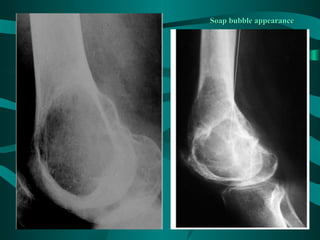

• X-ray:

– Expanding lytic lesion surrounded by a thin rim

of bone

– It may have a soap bubble appearance

Soap bubble appearance

• Pathology:

– Often involves the epiphysis of long bones

– Usually around the knee

– Red or brown mass with cystic degeneration

• Clinically: – Females>males – Age: 20-50 years – Bulky mass with pain and fractures • X-ray: – Expanding lytic lesion surrounded by a thin rim of bone – It may have a soap bubble appearance

• Pathology: – Often involves the epiphysis of long bones – Usually around the knee – Red or brown mass with cystic degeneration